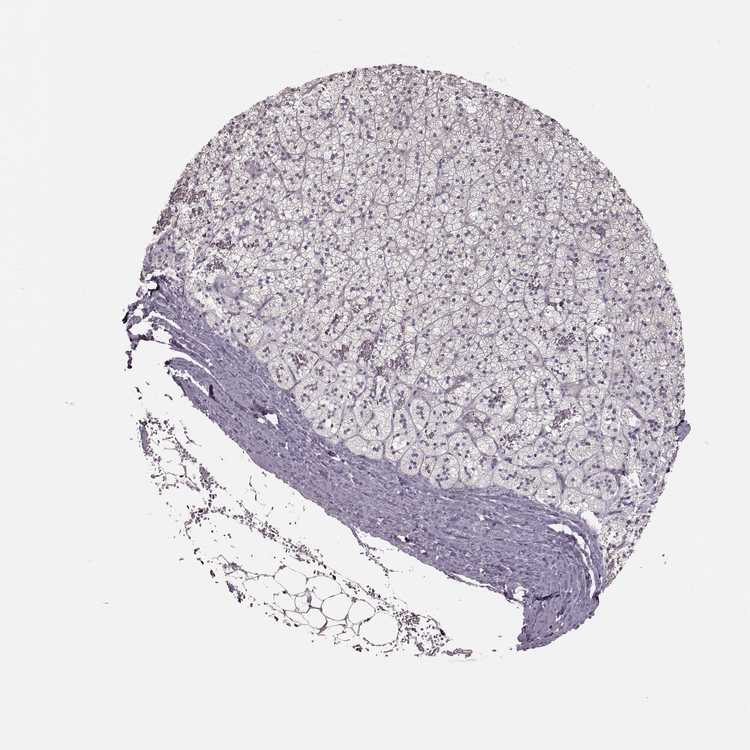

ADRENAL GLAND - Antibody stainingi

Antibody staining in the annotated cell types in the current human tissue is reported as not detected, low, medium, or high, based on conventional immunohistochemistry profiling in selected tissues. This score is based on the combination of the staining intensity and fraction of stained cells.

Each image is clickable and will lead to virtual microscopy that enables deeper exploration of all samples and also displays staining intensity scores, fraction scores and subcellular localization as well as patient and tissue information for each sample.

Antibody HPA070003

Glandular cells Not detected